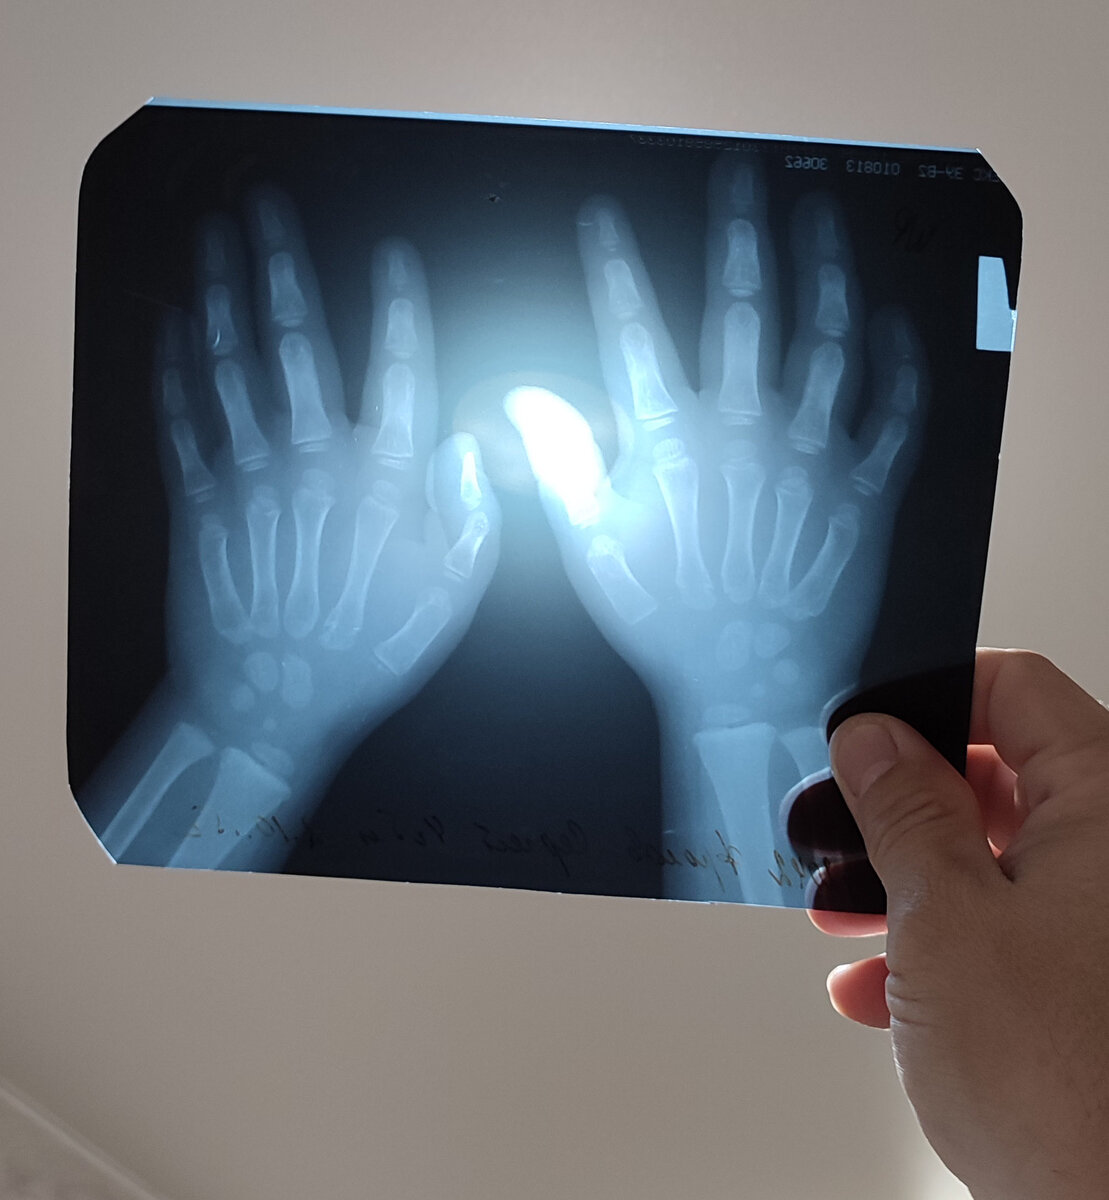

Тяжёлые фартуки были надеты, маленький Миша уже сидел у мамы на коленях. Руки с растопыренными пальцами, как показал дядя доктор, он положил на особый стол. Страшно уже не было, было жутко интересно. Сейчас сквозь него пройдут какие-то лучи и от этого руки станут как у скелета. На фотографии, конечно, но всё равно круто!

-До свидания, дядя Миша,- мальчик с гордостью прижимал к себе рентгеновский снимок, на котором отчётливо были видны его собственные кости.